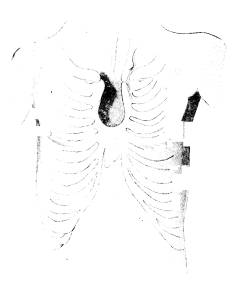

Bröstbenets uppkomst ur pariga anlag lämnar ock

en förklaring af en s. k. missbildning, hvilken

under namn af bröstbensspringa (fissura sterni)

stundom anträffas hos människan (fig. 119). I

dylika fall hafva af en eller annan anledning de

två bröstbenslisterna under fosterutvecklingen

ej fullständigt förenats, utan en större eller

mindre lucka kvarstår som en rest af den

ursprungliga stora luckan. Midten af brösthålan

beklädes, såsom i det afbildade fallet, endast

af huden, genom hvilken hjärtats pulsationer

omedelbart blifva synliga.

Fig. 119. Människa med bröstbensspringa <b(efter O. Schultze).

(efter O. Schultze).